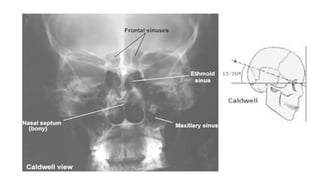

Caldwell view [occipito frontal with 15 deg caudad]

• This projection is used to demonstrate the frontal

and ethmoid sinuses.

• Positioning of patient :

• Patient is seated facing the erect bucky

• Neck is flexed to bring nose and forehead in contact

with the bucky.

• orbito meatal line perpendicular to the bucky,

• Central ray :

• Ray is directed perpendicular to the bucky along

the median sagittal plane.

• The tube is rotated 15 deg caudal to the orbito

meatal baseline

• centered 1/2 inch below the external occipital

protruberance

Caldwell view [occipitofrontal with 15 deg caudad] • This projection is used to demonstrate the frontal and ethmoid sinuses. • Positioning of patient : • Patient is seated facing the erect bucky • Neck is flexed to bring nose and forehead in contact with the bucky. • orbito meatal line perpendicular to the bucky,

• 20.

• Central ray: • Ray is directed perpendicular to the bucky along the median sagittal plane. • The tube is rotated 15 deg caudal to the orbito meatal baseline • centered 1/2 inch below the external occipital protruberance